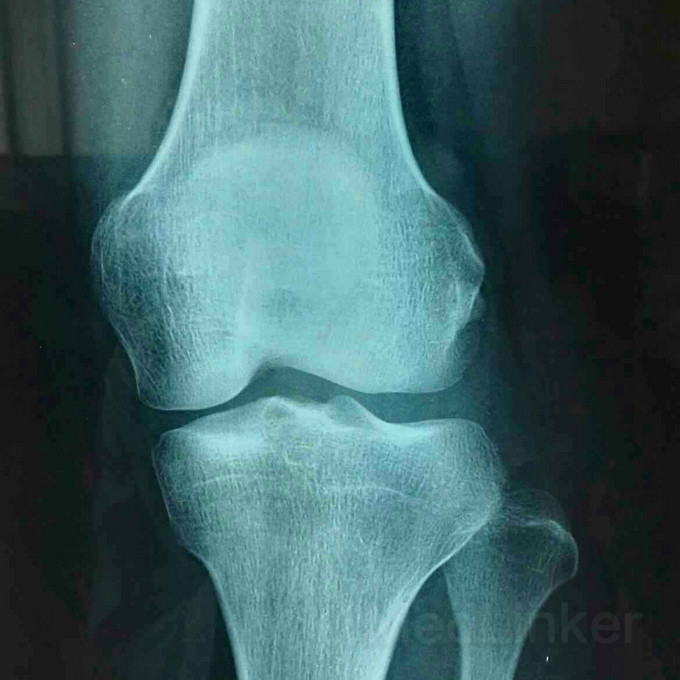

患者女,19岁,双膝关节习惯性髌骨脱位10余年,多家医院建议手术治疗,2个月前摔伤致左髌骨脱位,于某院行手术治疗,经家人商讨后决定再行右膝手术治疗来我院。请老师们指点是否需要调整髌骨远端力线?做何手术最为简单有效?具体是做单纯外侧支持带松解?外侧支持带松解+内侧关节囊缩紧筋膜成形?外侧支持带松解+髌腱手术?外侧支持带松解+胫骨结节内移?还是外侧松解+内侧紧缩成形+胫骨结节内移?还是什么?